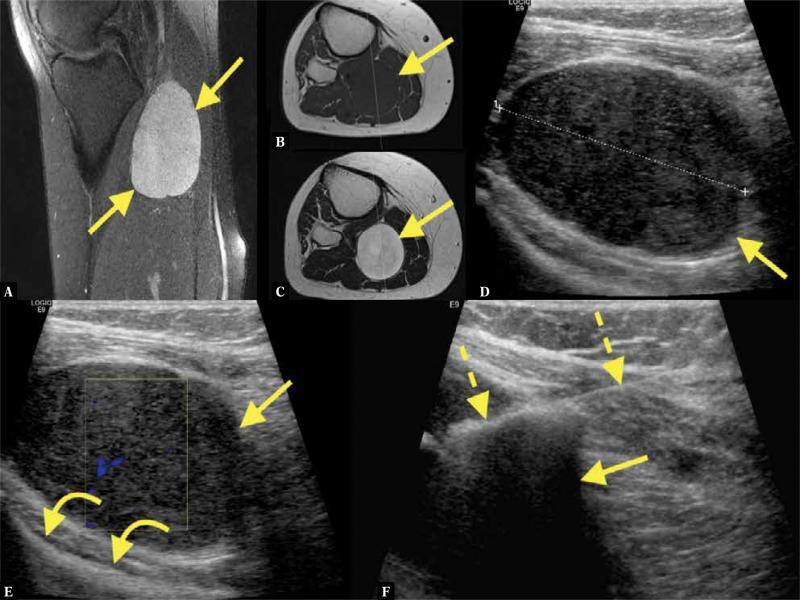

Fig. 6.

A 32-year-old patient presented with a painful mass in the popliteal fossa. MRI revealed an intramuscular tumor ( A–C ; straight arrow – tumor). Ultrasound showed a large hypoechoic mass ( D ). After suspicion of neurogenic tumor, the patient was referred for US-CNB ( E, F ; curved arrows – posterior surface of the tibia, dashed arrows – biopsy needle). The histopathological diagnosis was neuroma